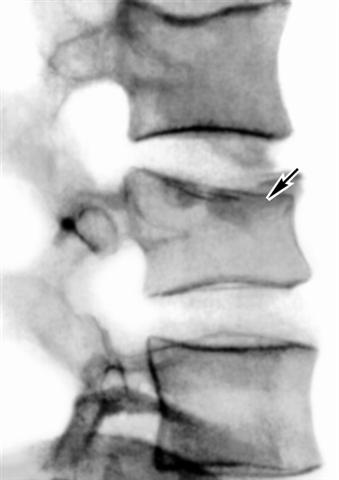

Рис. 10а). Рентгенограмма поясничного отдела позвоночника (боковая проекция) при компрессионном переломе со средней степенью компрессии: стрелкой указано тело поврежденного позвонка.